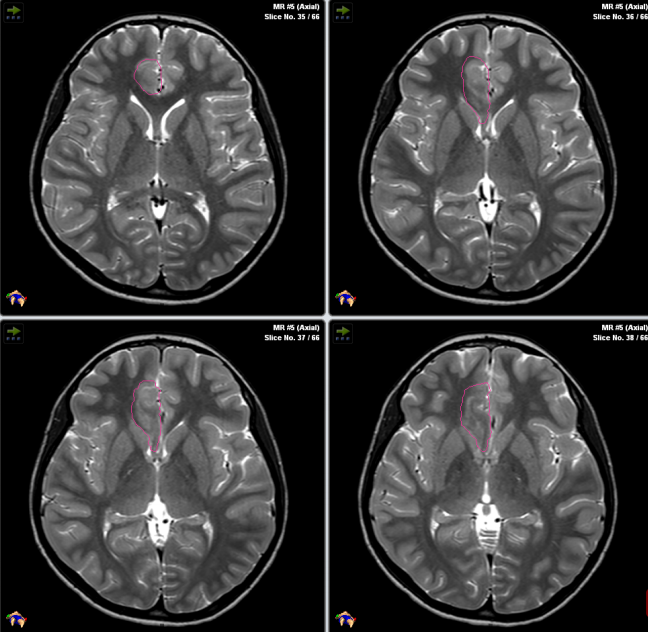

这是一名患有下丘脑错构瘤(HH)的两岁半患儿,肿瘤造成其痴笑样癫痫频发,且父母表示服用药物也无法抑制,但他们担心开颅手术会造成并发症,而且孩子年纪较小,术后护理难度更大,因此希望Rutka教授为孩子行激光间质热疗,在教授和其团队成员的努力下,患儿的脑瘤得到了极大程度的消融,术后患儿身体恢复很快、生长发育正常,而且癫痫也并未复发。

再按照手术方案设定手术入路轨迹后,插入激光探针准备消融

术中核磁共振监测下的激光消融全程热成像图

激光间质热疗(LITT)过程:(A)描绘左侧海马硬化的轴向T2加权和矢状面衰减倒置恢复(FLAIR)磁共振成像(MRI)切片。(B)通过枕骨入路沿海马长轴插入的激光探针。(C)激光消融后获得的早期T1对比增强MRI显示病变的大小。